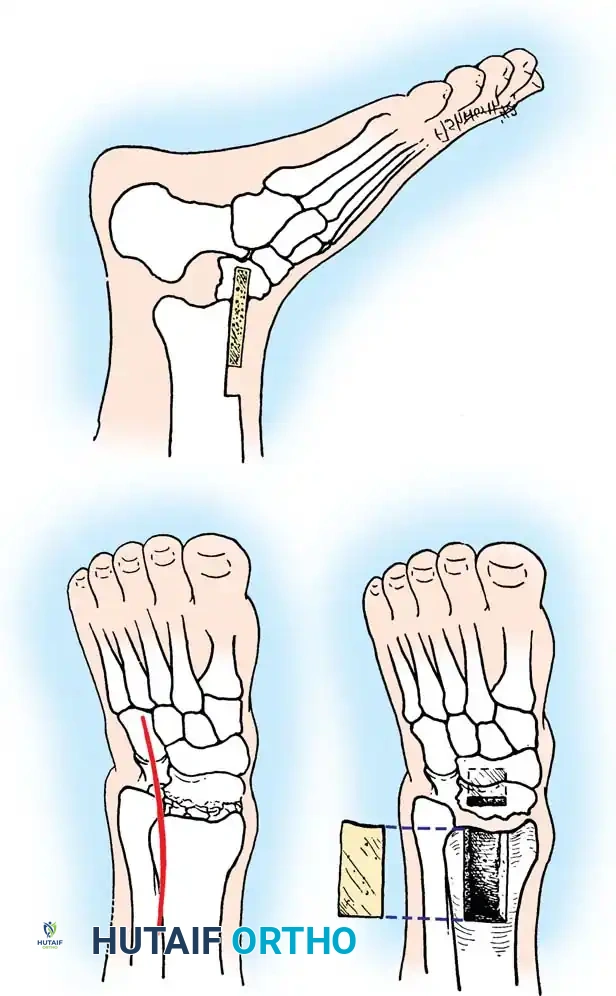

Surgical approaches diagram

1. Anteromedial Approach: An incision is made medial to the tibialis anterior tendon, extending from the medial malleolus to the navicular. This exposes the medial talar neck. Crucial: Dissection must not extend inferiorly to the deltoid ligament, as this protects the critical deltoid arterial branches supplying the talar body.

2. Anterolateral Approach: An incision is made in line with the fourth ray, lateral to the extensor digitorum longus (EDL) and superficial peroneal nerve. This allows visualization of the lateral talar neck and the subtalar joint.

Pitfall: Relying solely on a medial approach often leads to a varus malunion. The medial cortex is frequently comminuted. If compressed without restoring the lateral column length (visualized via the anterolateral approach), the talar neck collapses into varus, leading to devastating loss of subtalar eversion and chronic lateral foot pain.